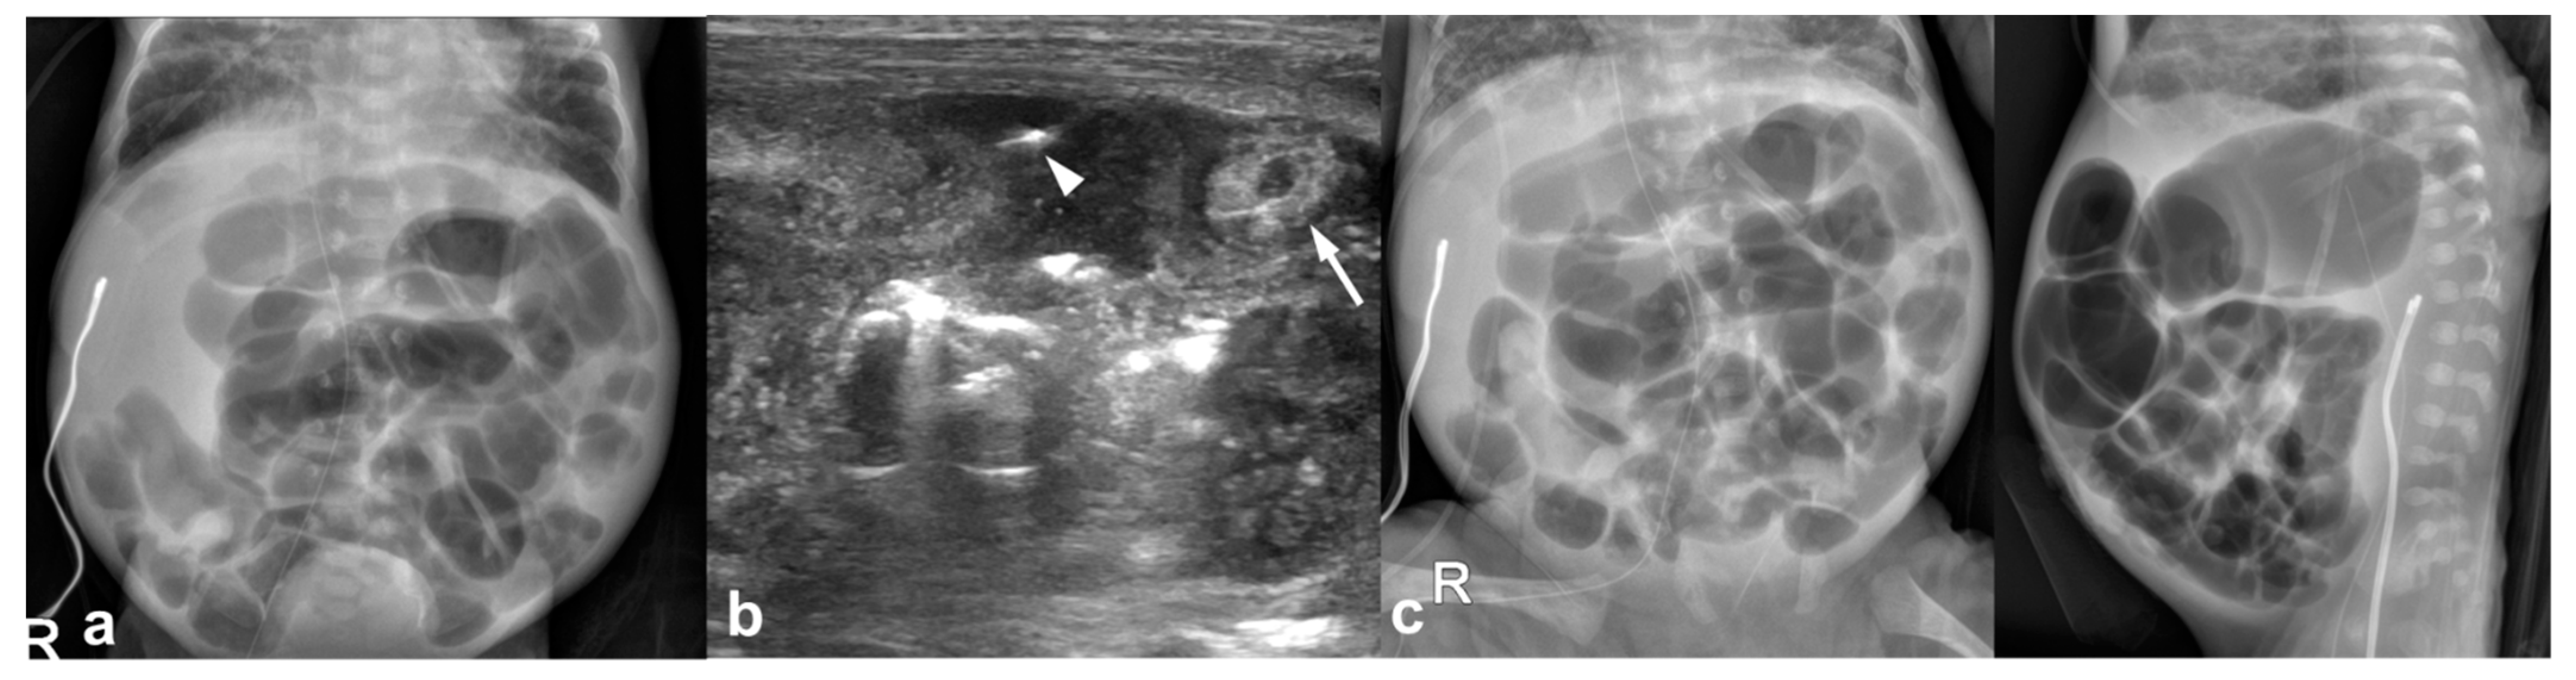

3.2. Imaging Findings

3.2.1. Abdominal Radiographs

3.2.2. Temporal Relation between Abdominal Radiographs and Bowel US